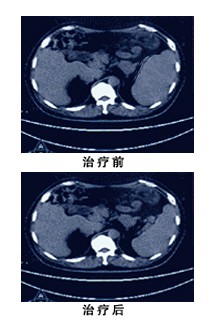

病人手术后经4个疗程的化疗后,采用WB-1无创全身热疗系统进一步治疗预防肿瘤复发。经2个疗程的WB-1无创全身热疗系统治疗,病人已经基本康复并能正常上班。最近PET-CT检查结果显示:病人体内没有残存肿瘤。病人的肿瘤标志物也在正常范围。